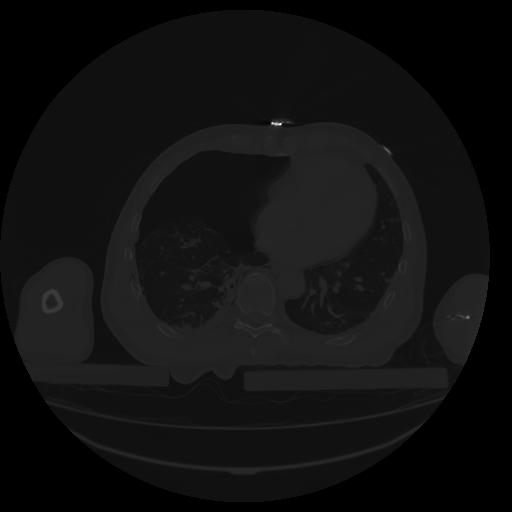

34 CUERPO,CE,Vol,1.0,CUERPO,,